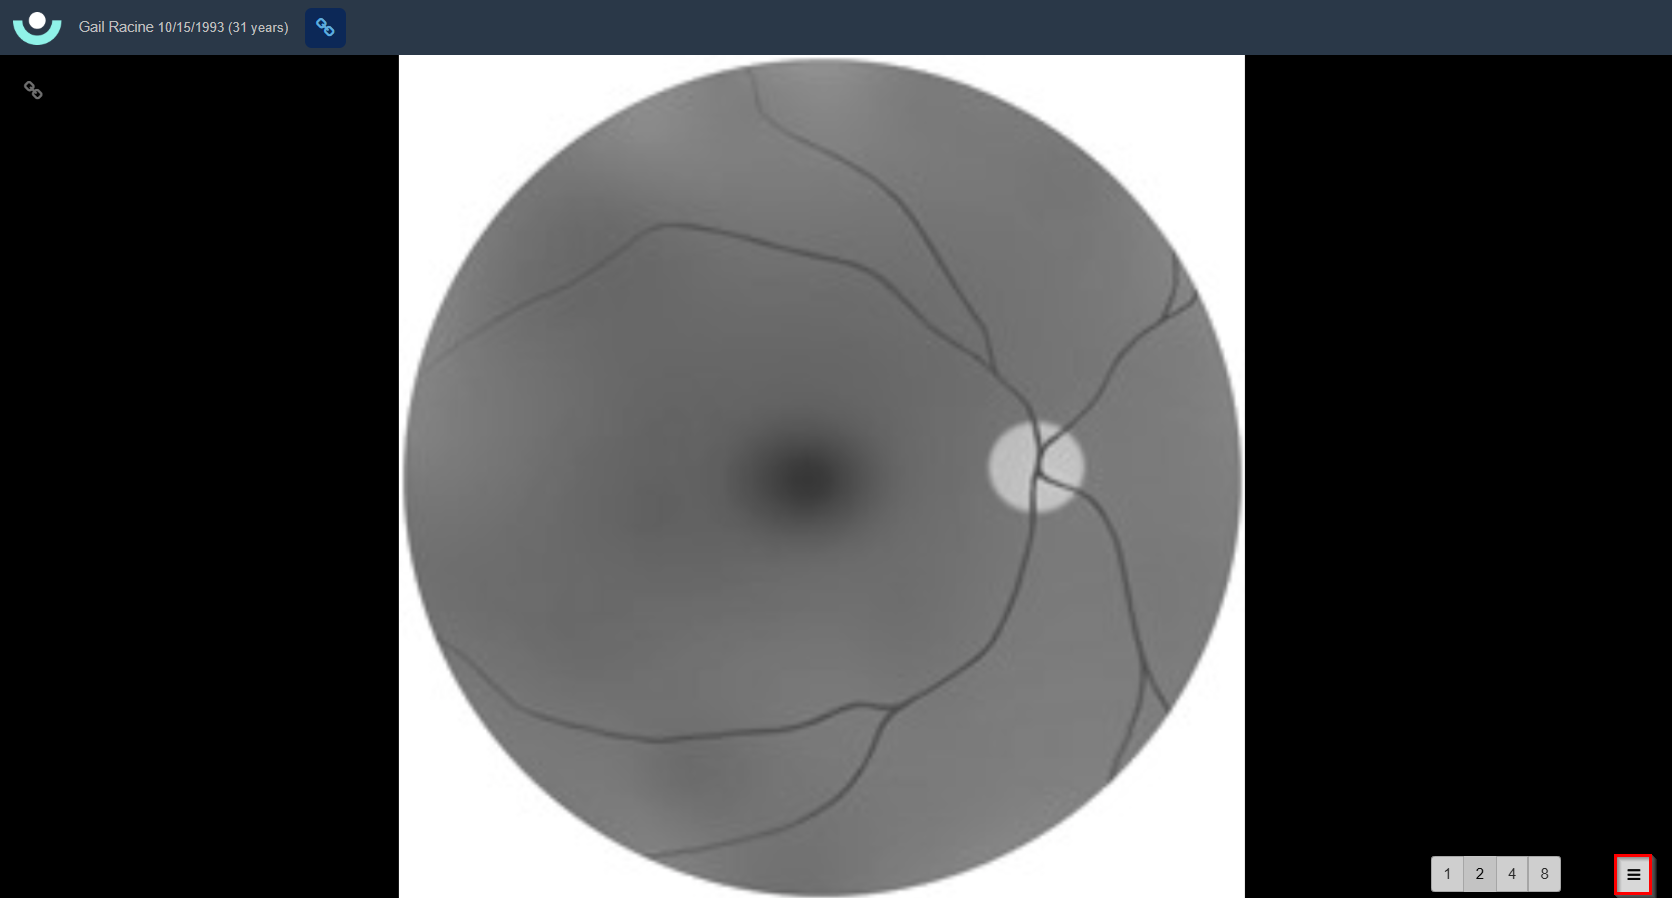

- The main viewer can be set to display 1, 2, 4, or 8 images at once by toggling the view options in the bottom toolbar. The number of images displayed is dependent on the screen size. See Example